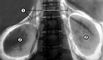

Диагностический пневморетроперитонеум используется главным образом для выявления опухолей надпочечников, а также пороков развития и других патологических изменений почек (рис. 1, 2) в тех случаях, когда не удается провести ультразвуковое исследование (см. Ультразвуковая диагностика), компьютерную томографию и ангиографию. Диагностические возможности пневморетроперитонеума увеличиваются при его сочетании с экскреторной урографией, ретроградной пиелографией, томографией.